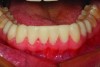

Fig 22. A preoperative retracted full-arch view of the patient’s teeth slightly separated to show the incisal edges of the maxillary and mandibular teeth. Note the supereruption of the mandibular anterior segment and dual plane of occlusion on the lower arch.

Figure 22

Fig 23. Compare this postoperative retracted full-arch view with Figure 22. The mandibular occlusal-incisal plane is more continuous with correction of the dual plane of occlusion and curve of Spee. The maxillary restorations give the illusion that the teeth themselves are smaller with a more natural progression of incisal embrasures and gradual apical movement of the contact areas moving from the midline toward the posterior segment, giving a more youthful appearance.

Figure 23